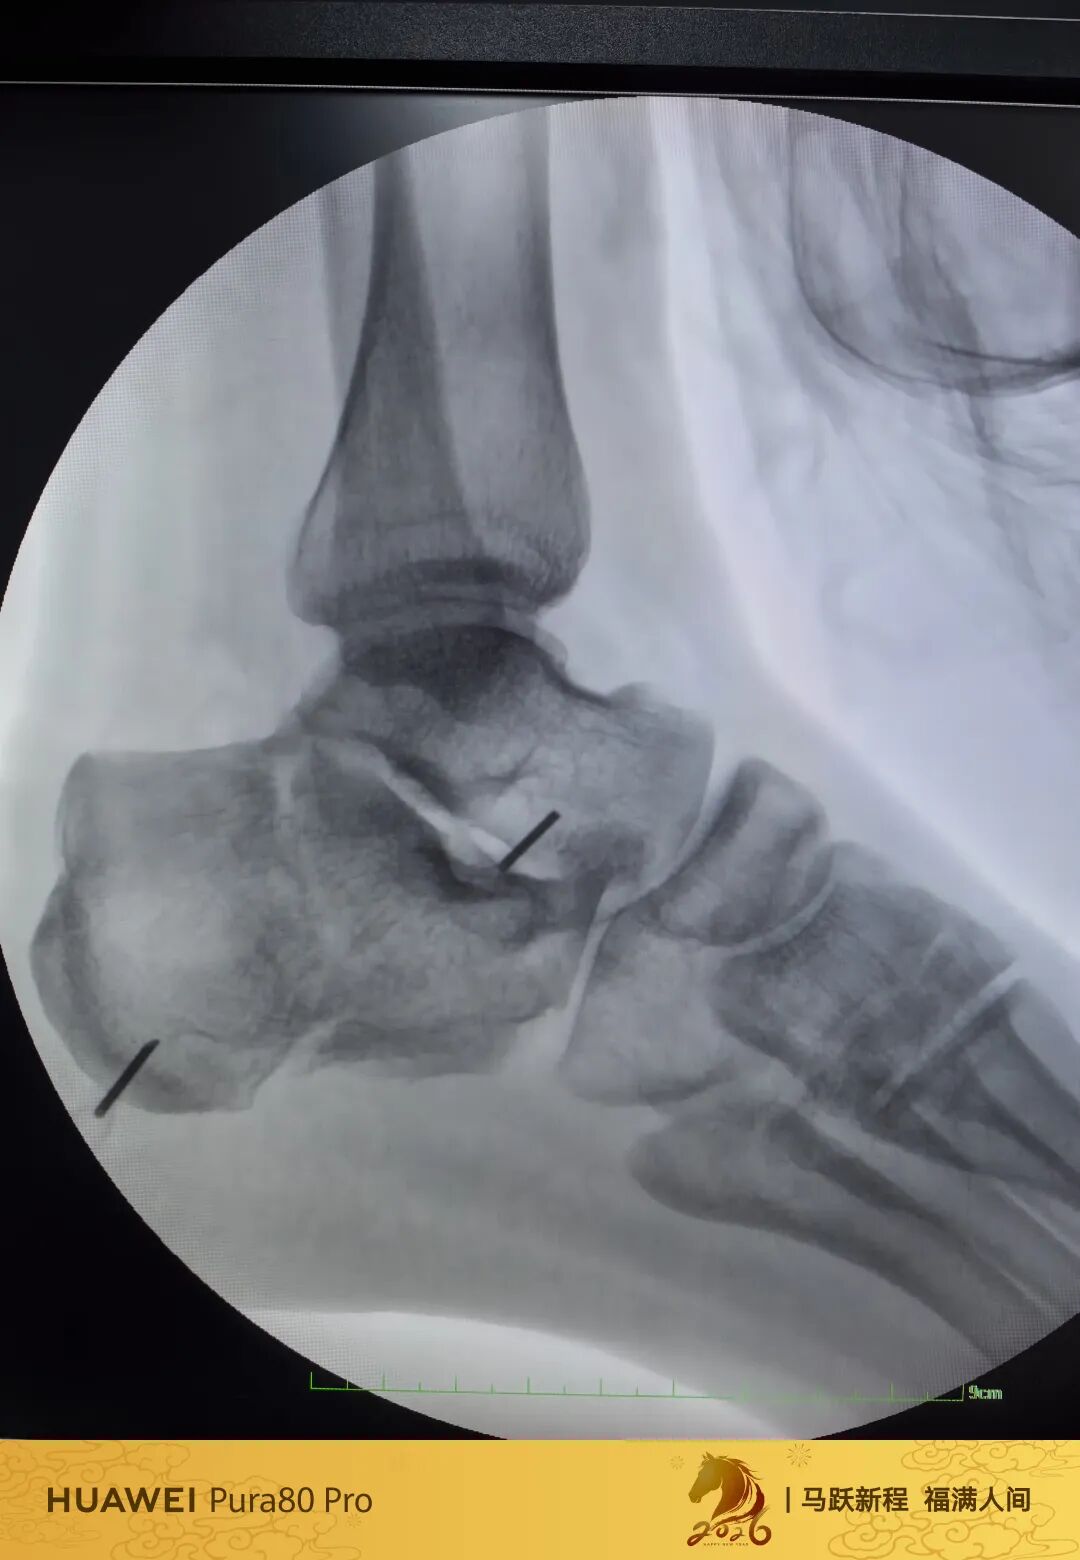

第60例跟骨微创了,虽然已经彻底放手,尽量只动嘴,但还是有小问题小瑕疵,无法完全避免。